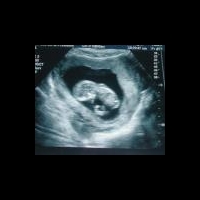

Ребенок прооперирован в утробе матери на сроке 26 недель

Испанские врачи провели эндоскопическую операцию плоду, развивающемуся внутриутробно в организме матери. На момент хирургического вмешательства срок беременности составлял 26 недель и масса плода около 800 грамм.

Известно, что операция была проведена в 2010 году, однако только в настоящее время хирурги сообщили об успешном результате операции: на данный момент девочка полностью здорова и ей исполнился 1 год.

Во время антенательной скрининговой диагностики развития плода и матери, гинекологи обнаружили по данным УЗИ аномалии развития легкого. В правом легком было нарушено строение бронхолегочной системы. Прогноз жизни ребенка после рождения был неблагоприятный и составлял несколько часов жизни. Частота данной аномалии развития новорожденных составляет 1 случай на 10 000 новорожденных. Смерть наступает в 90%.

Родители девочки дали согласие на операцию, опыт проведения которой отсутствовал во всех клиниках. Длительность операции составила около 30 минут. Хирурги ввели эндоскоп через ротовую полость плода и устранили преграду, препятствующую свободному прохождению воздуха в бронхи.

Через 11 недель после внутриутробной операции на свет появилась девочка, которую назвали Алаиз, что в переводе с баскского языка означает "радость".